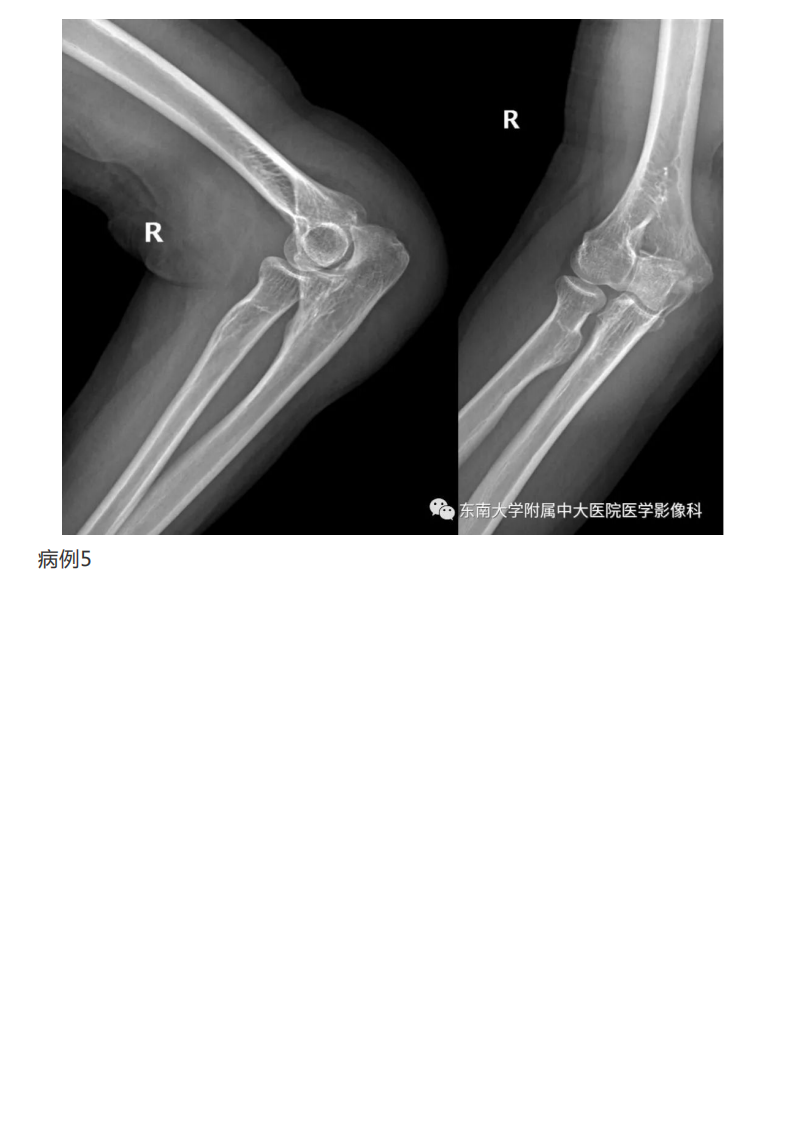

20190409_2【晨读结果公布】2019.04.08肌骨系统疾病.pdf